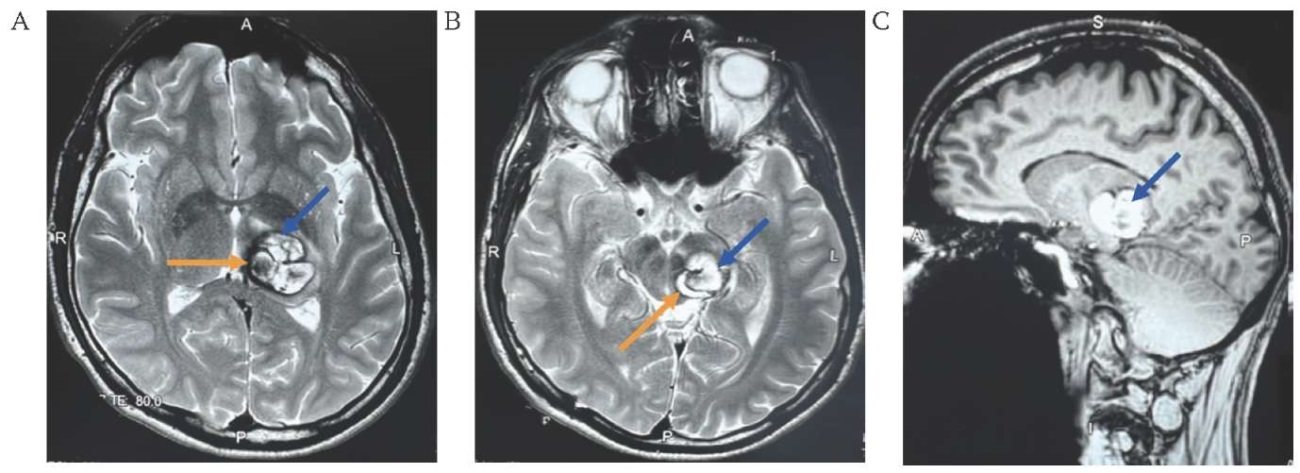

На компьютерной томографии (КТ) головного мозга выявлено нечетко ограниченное гиперденсное образование в нижней части дорсальной поверхности левой ножки среднего мозга размером 20×30×25 мм. По данным МРТ головного мозга выявлено гиперинтенсивное поражение в T1- и T2-взвешенных изображениях с четко определенным гипоинтенсивным ободком, гематомы в каверноме 20×30×25 мм (рис. 1A–C).

РИС. 1. Магнитно-резонансная томография пациента 38 лет с кавернозной мальформацией размером 20×30×25 мм в дорсальной части левой ножки среднего мозга (13.05.2024).

A, В. Аксиальные срезы, T2-взвешенное изображение: кавернозная мальформация (синяя стрелка), гематомы в каверноме (оранжевая стрелка).

С. Сагиттальный срез, T1-взвешенное изображение: кавернозная мальформация (стрелка).